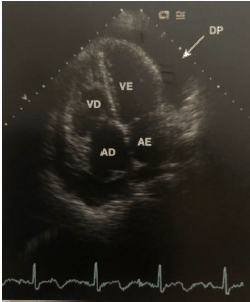

A imagem ecocardiográfica abaixo pode evoluir para uma emergência cardiológica que pode ter consequências graves, incluindo a morte. Baseado na figura abaixo, assinale a alternativa correta.

De acordo com a imagem ecocardiográfica abaixo obtida de um paciente jovem assintomático, em avaliação cardiológica de rotina, analise as afirmativas abaixo.

I. Os aneurismas congênitos do seio de Valsalva possuem formas regulares, com seios de paredes finas e invaginadas

II. A ruptura do aneurisma do seio coronário direito ocorre dentro do VD, a do seio coronário esquerdo ocorre dentro do AE e a do seio não coronário ocorre dentro do AD

III. Os aneurismas do seio coronário adquiridos são geralmente decorrentes de traumas torácicos e apresentam formato mais arredondado

IV. O fluxo na fistula da aorta tem seus componentes sistólico e diastólico bem marcados, refletindo a diferença das pressões entre a aorta e a câmara que recebe o fluxo